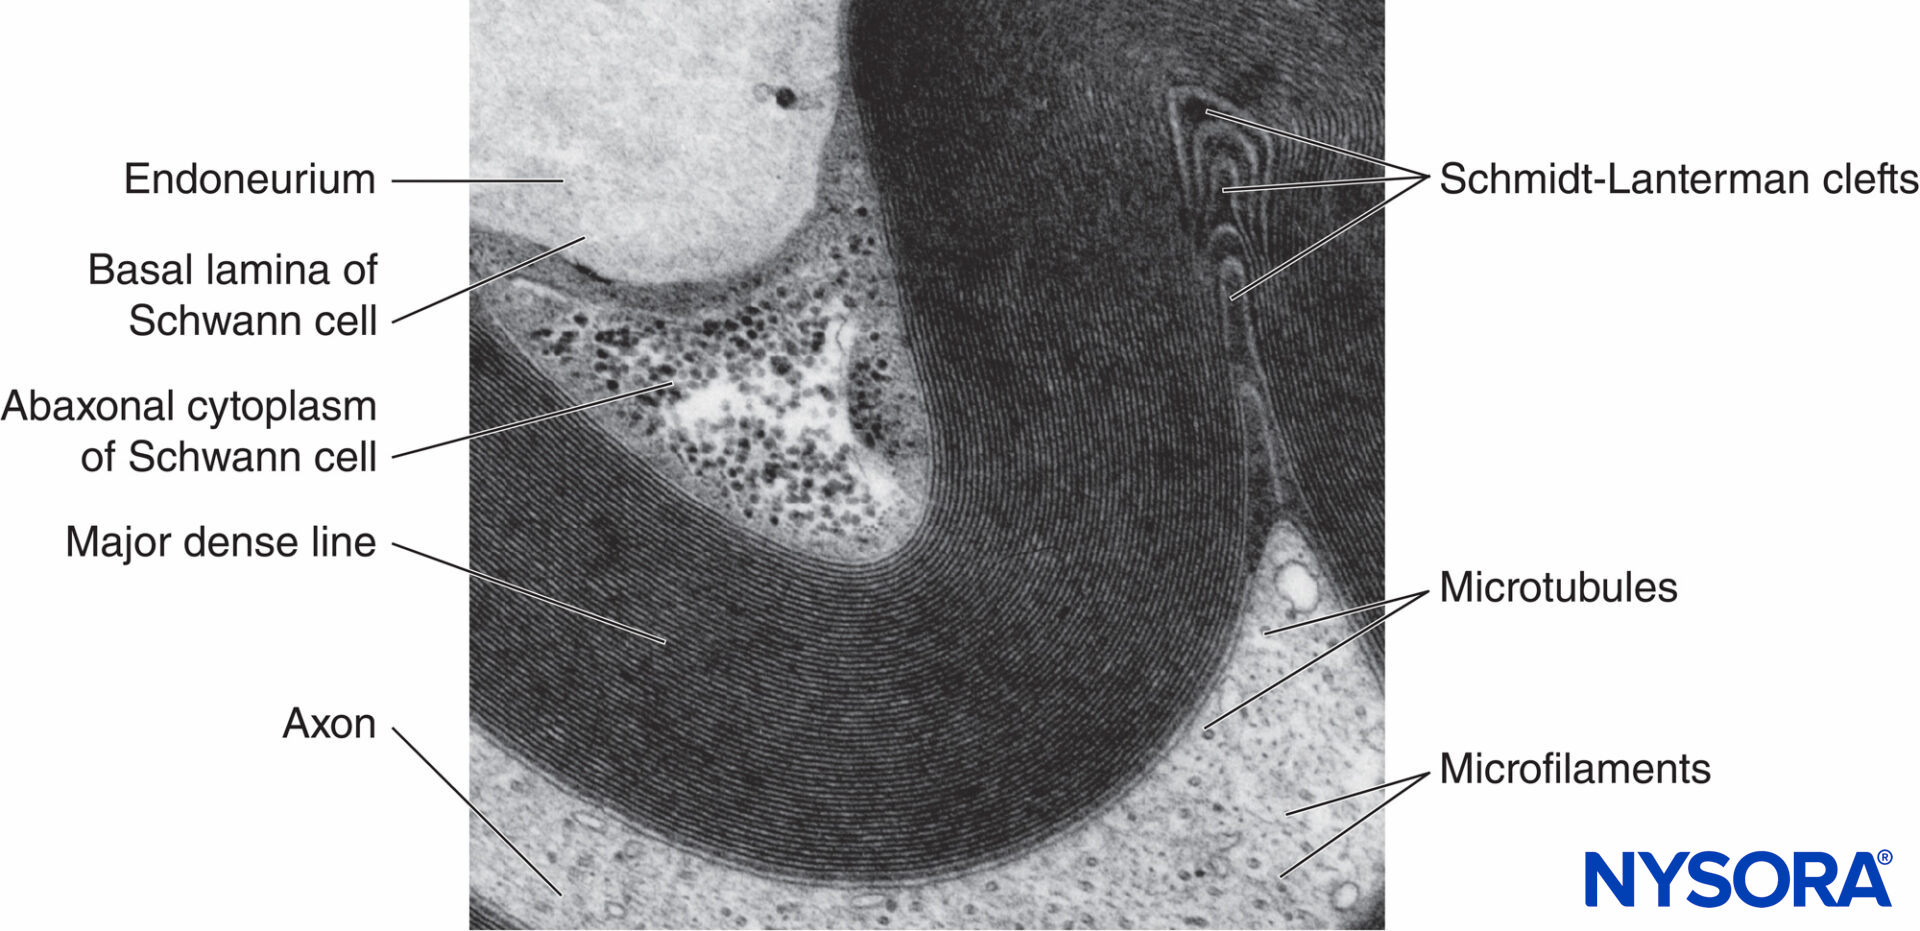

Myelinated nerve fibers are ensheathed by myelin, greatly extended and modified plasmalemma of the Schwann cells (Figures 4 and 5). Myelin formation begins with extension of the Schwann cell cytoplasm and development of the inner mesaxon, which wraps around the axon several times. During the wrapping process, the cytoplasm is nearly extruded between the plasmalemma. Apposing extracellular faces of plasmalemma become “the major dense line,” and apposing cytoplasmic faces form an “intraperiod line” of myelin. The proposed molecular structure of myelin fits the concept of plasmalemma as a lipid bilayer with integral and peripheral membrane proteins attached to the extracellular or to the cytoplasmic side of plasmalemma. In contrast to most biological membranes, myelin has a high ratio of lipid to protein (70%– 85% lipid, 15%–30% protein), where the latter serve as structural proteins, enzymes, voltage channels, and signal transducers.

FIGURE 5. Electron micrograph of the myelinated fiber. Myelin is visualized as a series of alternating dark and less-dark lines. Biopsy of human sural nerve.